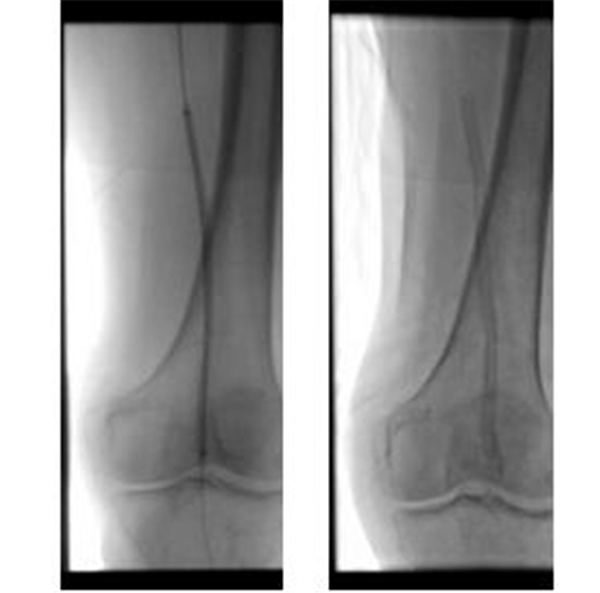

两位主任先用球囊扩张左侧股动脉狭窄段,再置入15厘米长的金属支架,上下端都超过狭窄段,如图~